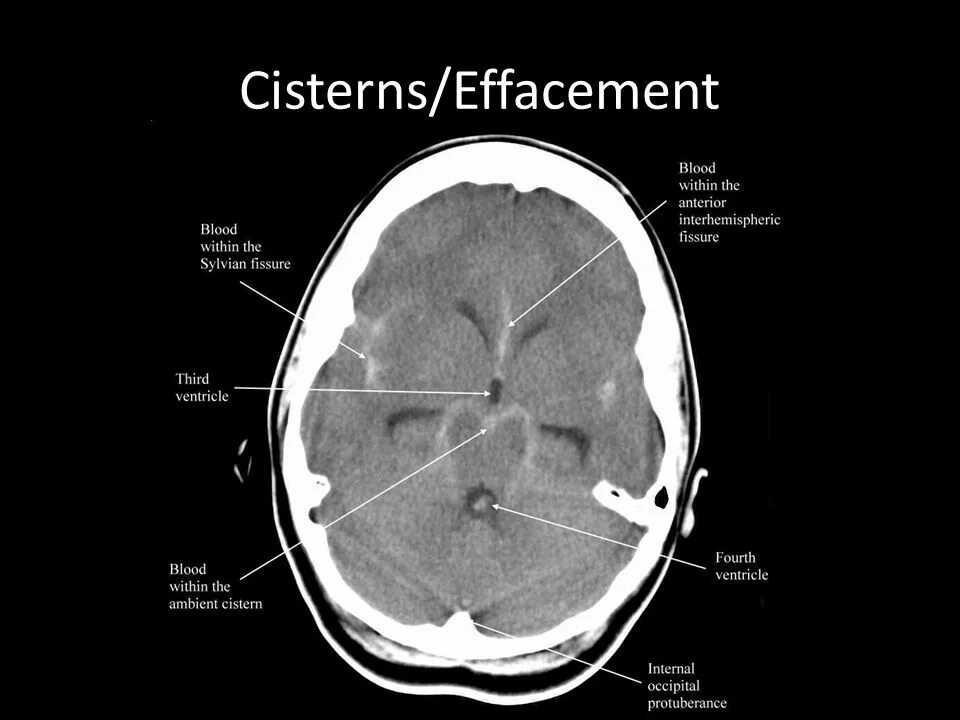

Цистерны на кт